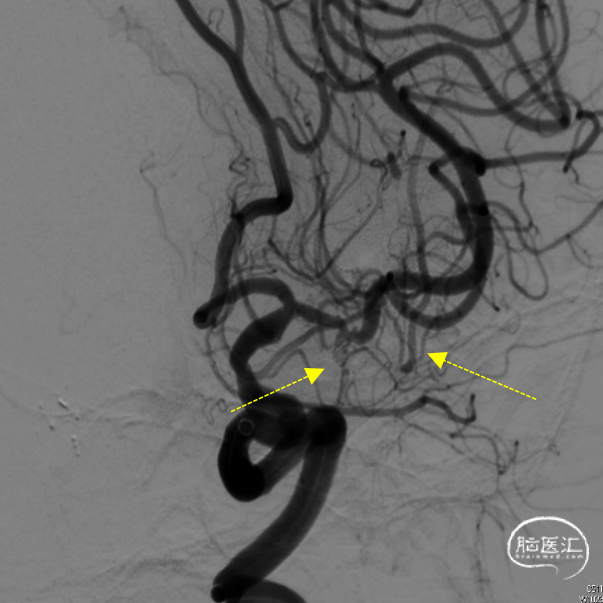

造影显示:颈内动脉迂曲,动脉瘤大小3.9×2.2mm,动脉瘤侧壁有边支发出,远端延续为较粗的向颞叶供血动脉(红色虚线)。

该患者颈内动脉迂曲,使用6F通桥银蛇DA远端通路导引导管(105cm),在0.035”超滑导丝配合下顺利到达岩骨段后继续送银蛇DA至海绵窦段,以便为手术提供有力支撑

6F通桥银蛇DA远端通路导引导管到位后,工作角度微导管抵近造影,证实动脉瘤侧壁发出的边支向颞叶供血。

微导管送入弹簧圈 3mm×4cm,意向性栓塞。空出侧壁的边支动脉起始部。同时使用另一条微导管在远离边支的瘤颈部填(弹簧圈1mm×2cm)。

动脉瘤大部填塞后,边支动脉血流完好。